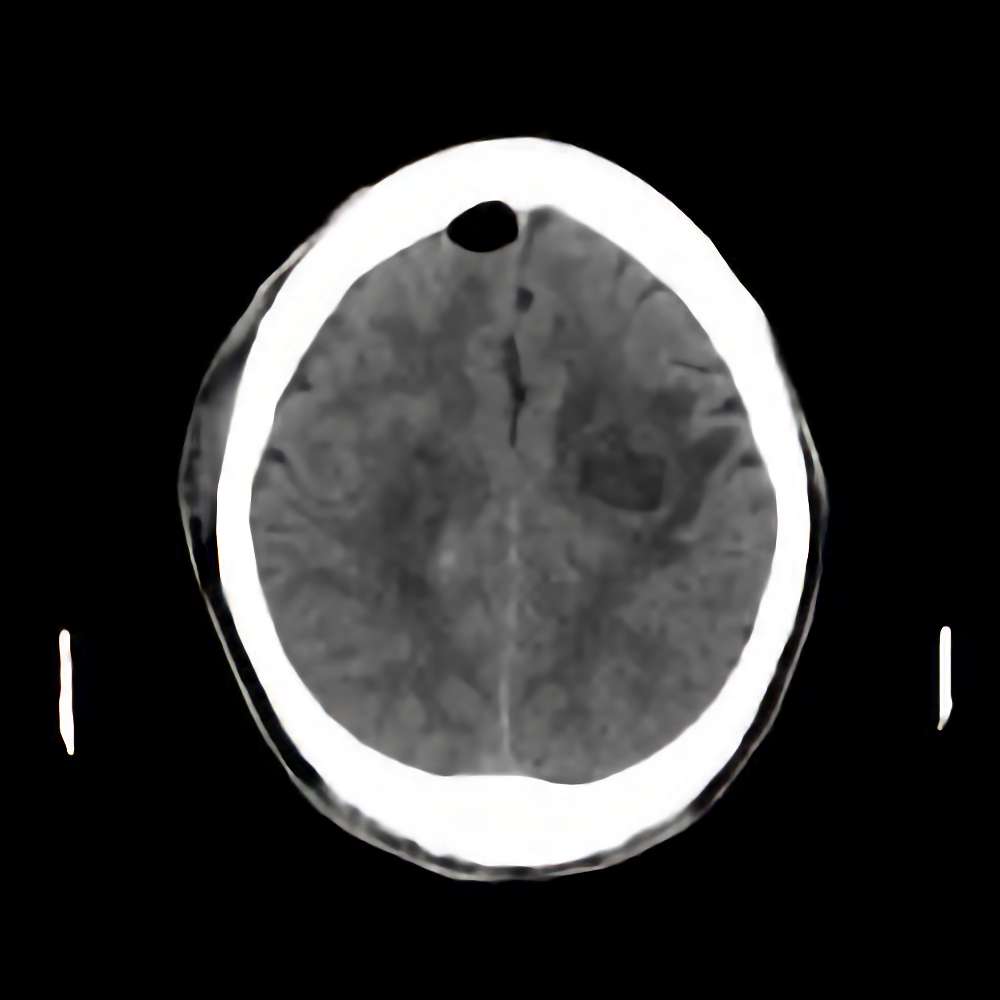

脳腫瘍

断層撮影

手術前1

No.’15_1 手術前1